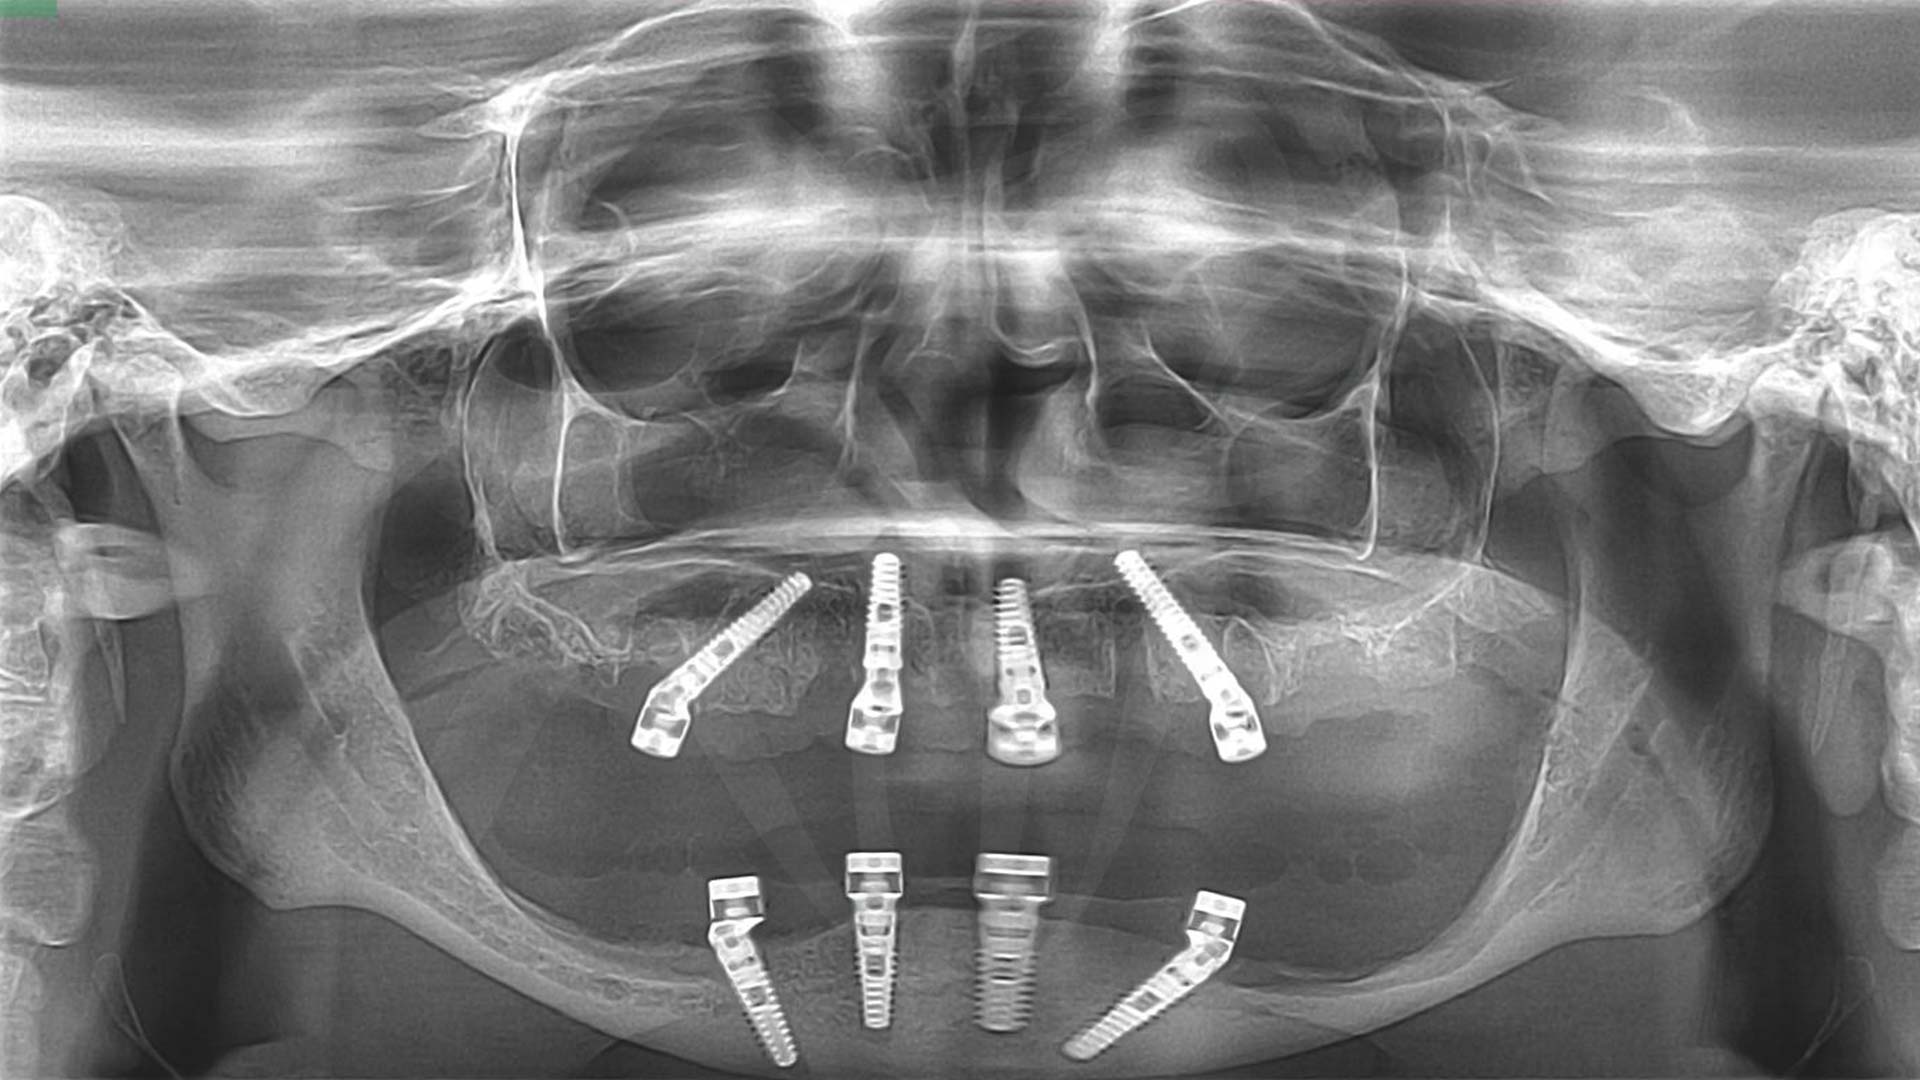

Az implantátumok behelyezését általában szikével történő metszés után lebenyes feltárásból végezzük. Azonban a digitális technika egyes esetekben ma már lehetővé tesz feltárás és varrás nélküli műtéti sablonnal végzett műtétet is. Mivel a beavatkozás előtt minden esetben rutin-szerűen 3 dimenziós rtg felvételt, CBCT-t készítünk, ennek adatai alapján amennyiben ezt a high-tech beavatkozást szeretné, – amely kevésbé véres, a műtét után kevésbé fájdalmas és kisebb a duzzanat,- akkor kérheti az implantációs sablonnal végzett műtétet.

A képek csak illusztrációk (a szájról készült fényképen cocr vázra égetett porcelán pótlás látható) a munkafolyamatok és a fogpótlás szerkezetének könnyebb megértése érdekében. Az ön fogpótlása csak hasonlóan fog kinézni, csak a jellege ugyanilyen. A szürke csavarozható elemek a mélyben látszódhatnak, a rózsaszín íny és a fogak átmenete hasonló lesz, de az elveszett csont és lágyrészek mennyisége, az íny lefutása, az implantátumok helyzete, helye mindenkinél más így a pótlás kinézete is változik.